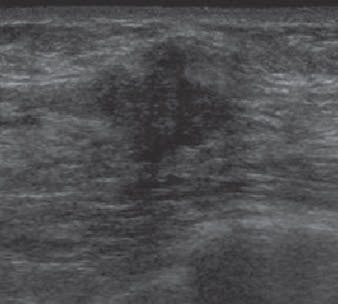

| Targeted ultrasound image above reveals solid mass with irregular shape and indistinct and angular margins. BI-RADS 5 assessment was made. Histopathology from ultrasound-guided core needle biopsy showed invasive ductal carcinoma. |